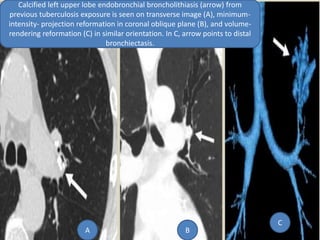

 Calcified or ossified material within the bronchial

lumen can cause focal bronchiectasis. By far the

most common cause of broncholithiasis is erosion

by and extrusion of a calcified adjacent lymph

node, usually associated with a long-standing

focus of necrotizing granulomatous lymphadenitis,

especially after tuberculosis. Nevertheless, the

frequency of broncholithiasis complicating

granulomatous infection is quite low. The most

common sites are the proximal right middle lobe

bronchus and the origin of the anterior segmental

bronchus of the upper lobes because of airway

anatomy and lymph node distribution.

Calcified left upper lobe endobronchial broncholithiasis (arrow) from

previous tuberculosis exposure is seen on transverse image (A), minimum-

intensity- projection reformation in coronal oblique plane (B), and volume-

rendering reformation (C) in similar orientation. In C, arrow points to distal

bronchiectasis.